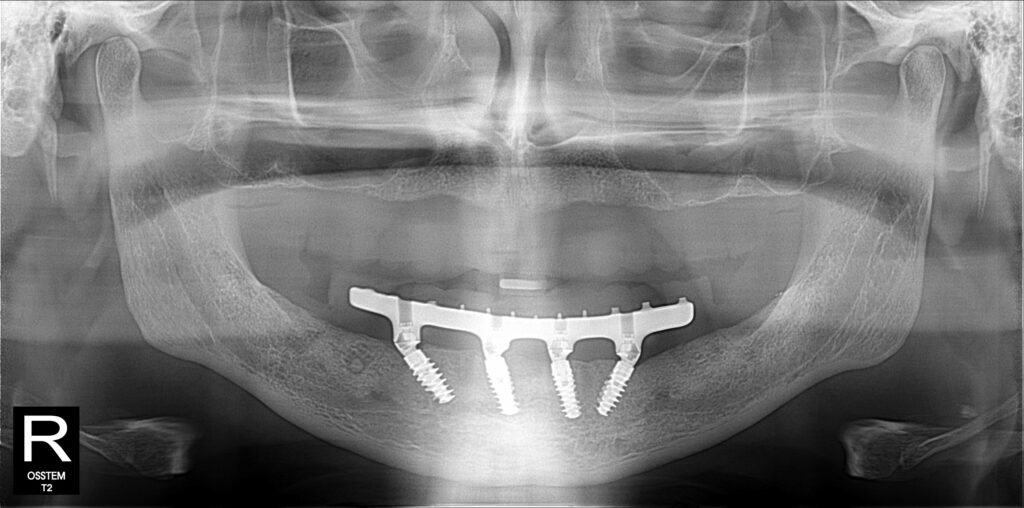

A selection of full arch fixed implant bridge patients after 5 years of wear

Oral Surgeons – Dr Han Choi, Dr Sam Goldsmith, Dr Rajiv Rajpal NSOMS

Prosthodontist – Dr Alan Payne NSOMS/Northland Prosthodontics

Dental technicians – Hosaka Takashi, DT Denture Design, Auckland, CJ Park, Project Dentistry, Auckland and Osteon Medical, Melbourne, Australia.